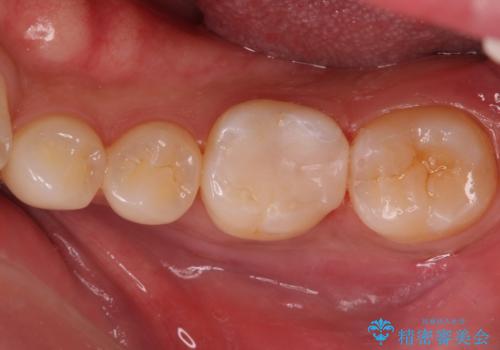

奥歯が欠けた セラミックインレーでの治療

治療前後で比べると、詰め物と歯の間のすき間もなくなりセラミックインレーの適合の良さが伺えます。